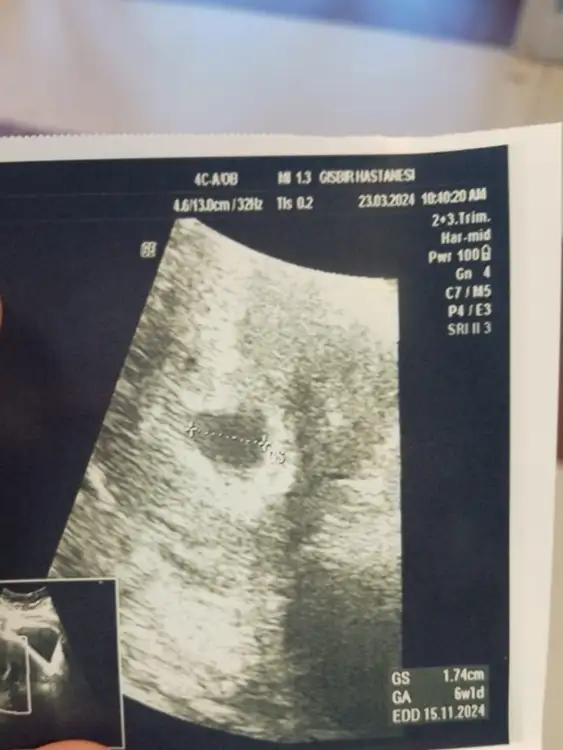

Slm kızlar rica etsem bana da bakarmısınız 5+6 karından bakıldı

• 1000057768.webp

• 1000057769.webp